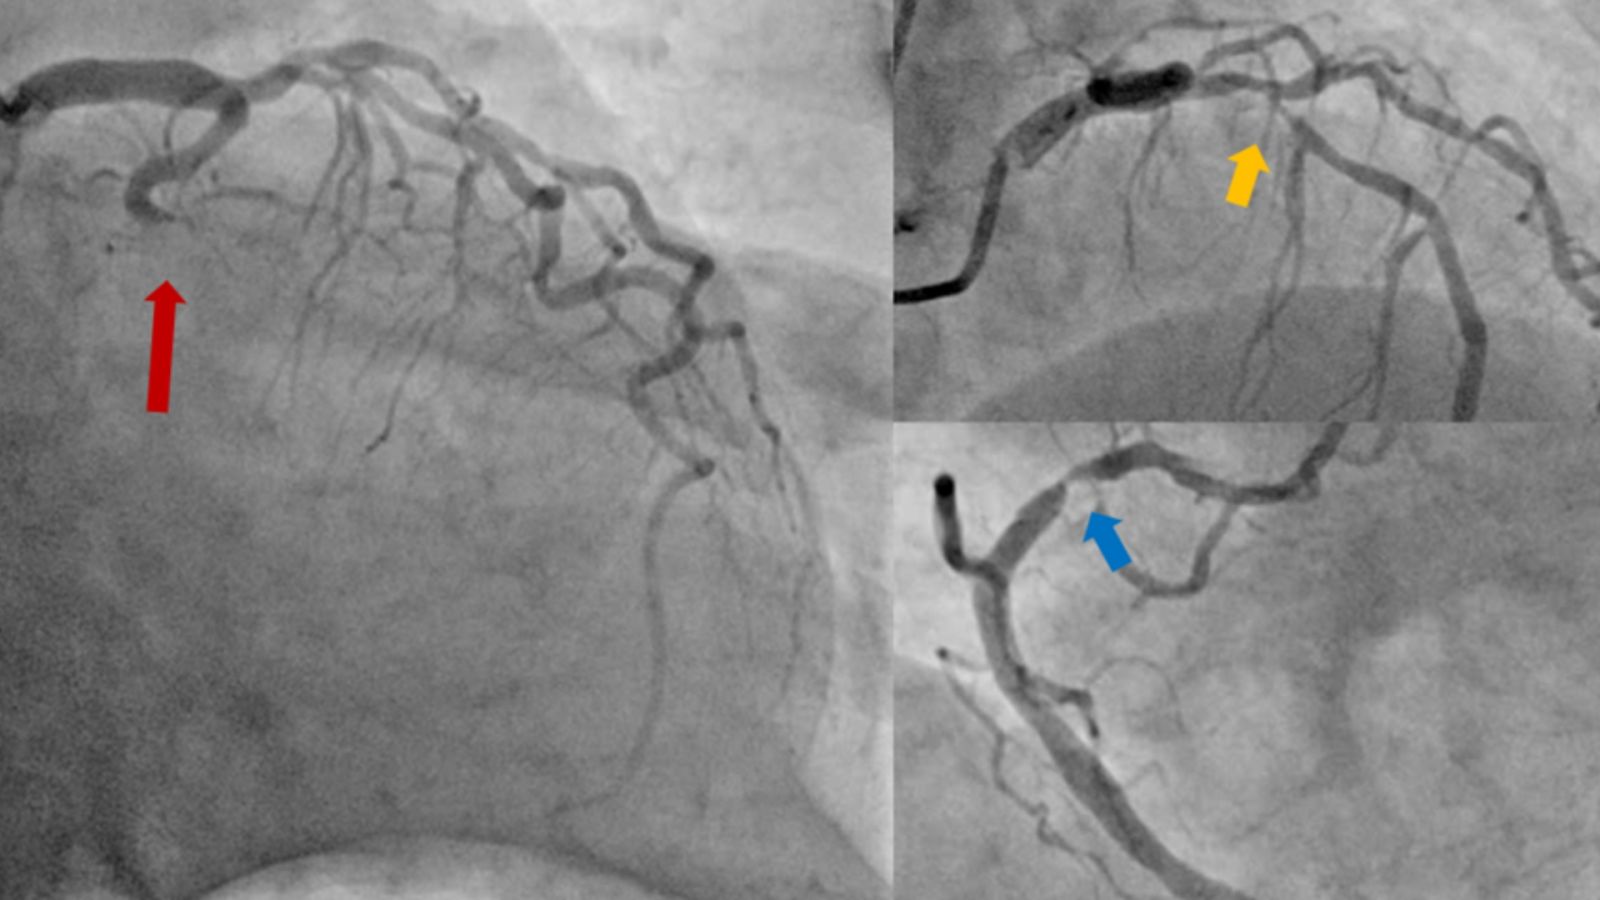

Hình ảnh chụp động mạch vành cho thấy tắc hoàn toàn động mạch mũ (mũi tên đỏ), hẹp nặng cả động mạch liên thất trước (mũi tên vàng) và động mạch vành phải (mũi tên xanh).

Người bệnh sau đó được đưa đến phòng DSA để được chụp động mạch vành cấp cứu. Kết quả chụp mạch vành cho thấy tắc hoàn toàn động mạch mũ, hẹp nặng động mạch liên thất trước và vành phải.

BS.CKI. Nguyễn Thanh Bình, Phó Trưởng khoa Nội Tim mạch nhận định: “Đây là trường hợp ngưng tim sau nhồi máu cơ tim, với thủ phạm là tắc hoàn toàn động mạch mũ, đồng thời hẹp nặng cả hai nhánh động mạch vành còn lại. Việc can thiệp tái thông hoàn toàn cả động mạch thủ phạm và hai động mạch hẹp nặng là phù hợp với các khuyến cáo hiện hành và sẽ giúp khả năng cứu được người bệnh cao hơn”.